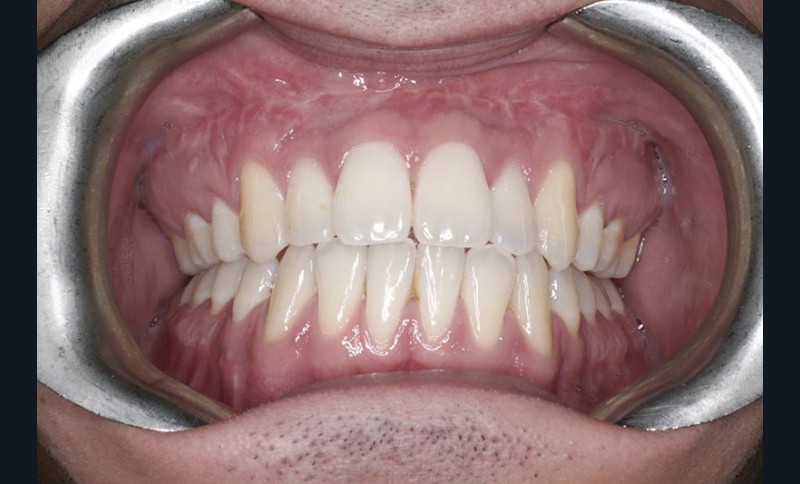

Olivier se présente à l’âge de 12 ans avec une classe III squelettique à prédominance mandibulaire, accompagnée d’une hyperdivergence et d’une endomaxillie responsable des inclusions des canines supérieures à forte obliquité. Une phase d’expansion est réalisée afin de permettre une augmentation du périmètre de l’arcade et la verticalisation des germes des canines. L’expansion permet en effet une normalisation transversale mais ne permet pas de réaliser la mise en place des canines. Les extractions des prémolaires sont alors effectuées et une préparation primaire de l’arcade supérieure par multi-attaches avec désinclusions et tractions des canines est réalisée.

Les résultats esthétiques et occlusaux satisfont amplement le patient qui revient pour un contrôle à long terme 10 ans après l’intervention montrant la stabilité des résultats.